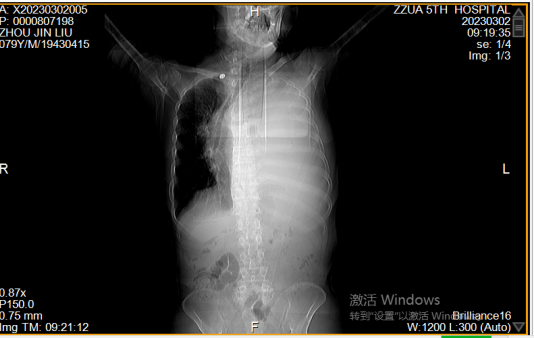

近日,郑州大学五附院呼吸与危重症医学科收治一位79岁 “胸腔积液”男性患者,该患者既往有“支气管哮喘”,此次以“胸闷、气喘20余天,加重2天”为主诉入院,门诊查胸部CT提示左侧大量胸腔积液,左肺压缩不张。如下图: